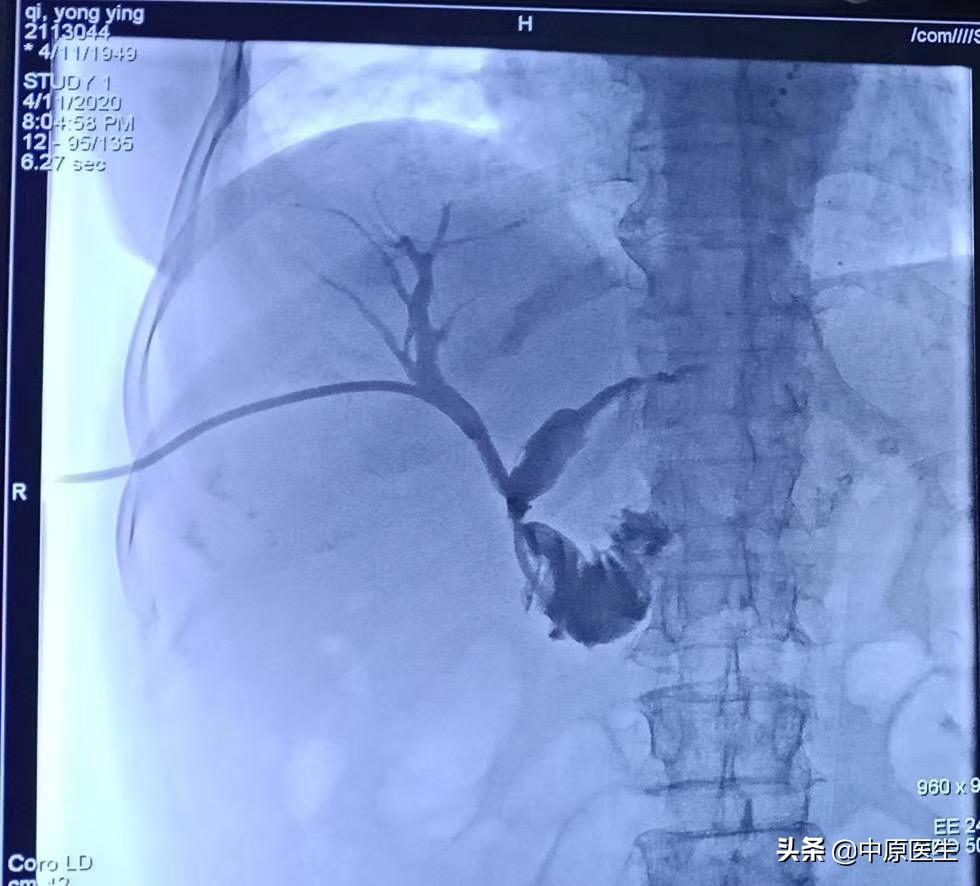

经过消化内科积极准备,病人当天晚上就躺了我们的术台上,那时的患者,正在寒颤,我们迅速消毒,铺巾,准备好手术器械,定位、局麻,从右侧胸壁腋中线第十肋间一针穿刺进入肝右胆管,依次送入扩张鞘,导丝,外引流管,随即就抽出了瘀滞的带味道(感染细菌发出来的味道)的墨绿色、带沉渣的胆汁和肠液约100多毫升。因为患者寒颤,身体情况太差,所以我们放弃了再仔细寻找狭窄肠管部位的手术(这时候保命要紧,那个手术可以择期再次进行),冲洗引流管后,固定、包扎。把患者安全转入介入科病房。回到病房十多分钟后,患者的腹胀、寒颤都有了明显减轻。精神状态也好了很多。看着自家老人转危为安,这一家子说了数不清感激的话!

我们做这个经皮穿刺胆管造影+引流管置入术(PTCD)是怎么一回事呢?它是在影像设备引导下,用一根21G(0.80mm)的细穿刺针经皮经肝穿刺胆管,并置入引流管,使胆汁流向体外或十二指肠的一系列技术。主要用于胆道梗阻和急性炎症的治疗。PTCD不受胆管手术影响(如胆肠吻合术等),对患者的身体要求相对较低,创伤小,缺点是对原发病的治疗有时候会力不从心。